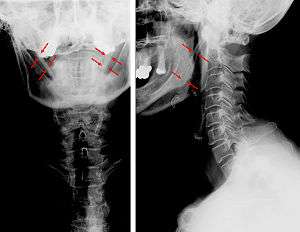

CT scan, coronal section showing bilateral extended styloid process and stylohyoid ligament ossification (incidental finding)

Diagnosis is suspected when a patient presents with the symptoms of the classic form of "eagle syndrome" e.g. unilateral neck pain, sore throat or tinnitus. Sometimes the tip of the styloid process is palpable in the back of the throat. The diagnosis of the vascular type is more difficult and requires an expert opinion. One should have a high level of suspicion when neurological symptoms occur upon head rotation. Symptoms tend to be worsened on bimanual palpation of the styloid through the tonsillar bed. They may be relieved by infiltration of lidocaine into the tonsillar bed. Because of the proximity of several large vascular structures in this area this procedure should not be considered to be risk free.

Imaging is important and is diagnostic. Visualizing the styloid process on a CT scan with 3D reconstruction is the suggested imaging technique.[6] The enlarged styloid may be visible on an orthopantogram or a lateral soft tissue X ray of the neck.